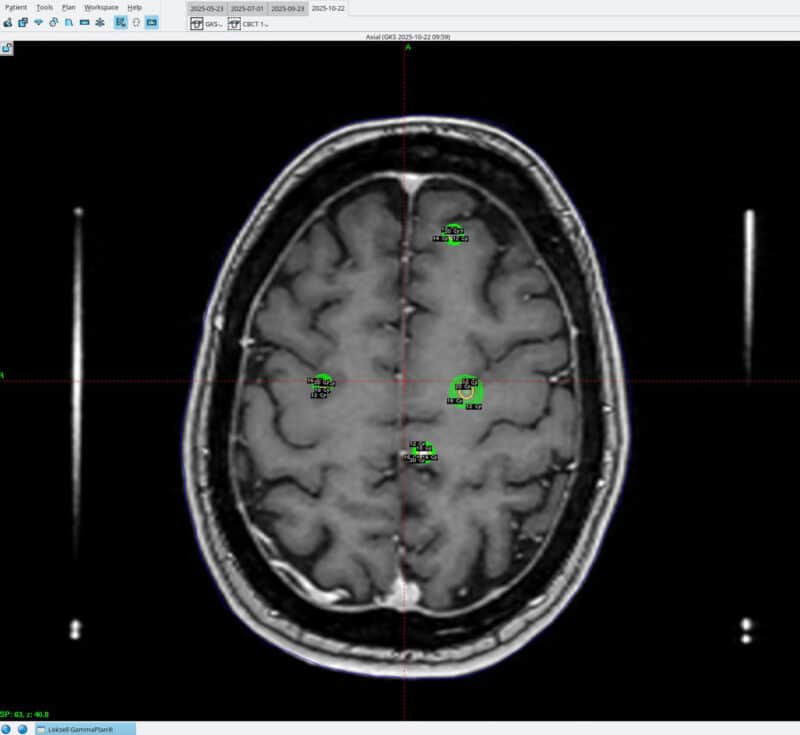

Amerikanske og europeiske retningslinjer anbefaler stereotaktisk strålebehandling fremfor helhjernebestråling hos pasienter med god funksjon (Karnofsky Performance Scale, KPS ≥ 70 eller Eastern Cooperative Oncology Group, ECOG ≤ 2) og begrenset intrakraniell sykdom (43, 46). De fleste studier inkluderer én til fire metastaser, men nyere data viser at opptil ti kan behandles trygt dersom samlet volum er under 15 ml (46, 47) (bilde 4). I praksis er derfor totalvolum viktigere enn antall lesjoner. Ved lavt metastasevolum og kontrollert ekstrakraniell sykdom oppnås høy lokal kontroll og bevart kognitiv funksjon.

Bilde 4: Stråleknivbehandling av fire hjernemetastaser, illustrert med randdosen (20 Gy) og dosefallet i grønne linjer (18, 16, 14 og 12 Gy). Bildet er gjengitt med samtykke fra pasienten.